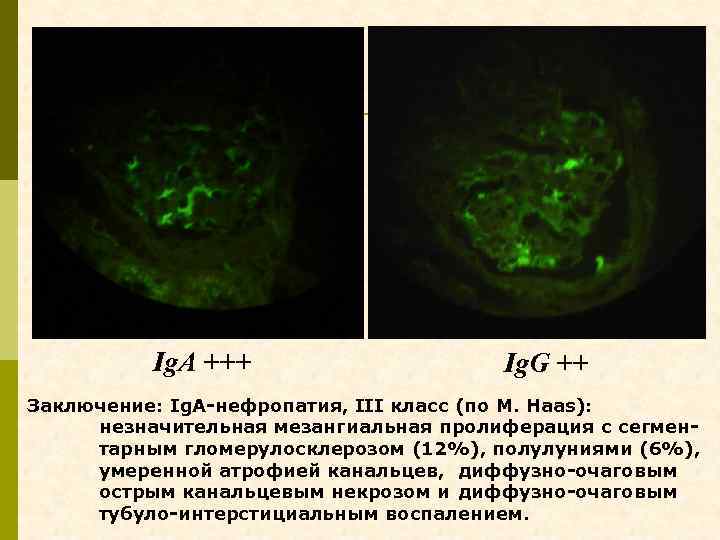

Ig. A +++ Ig. G ++ Заключение: Ig. A-нефропатия, III класс (по M. Haas): незначительная мезангиальная пролиферация с сегментарным гломерулосклерозом (12%), полулуниями (6%), умеренной атрофией канальцев, диффузно-очаговым острым канальцевым некрозом и диффузно-очаговым тубуло-интерстициальным воспалением.